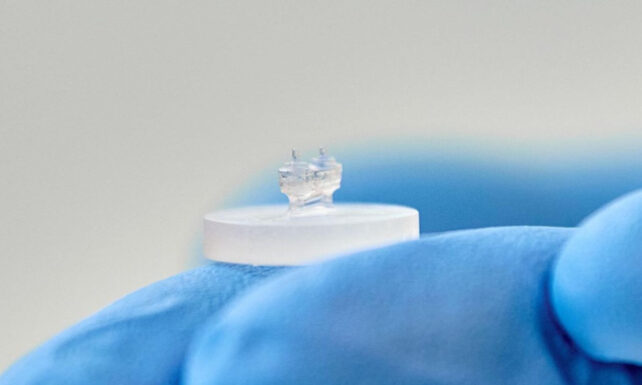

To construct their HOC models, the research team isolated cardiac muscle and connective tissue cells from rat subjects. These cells were subsequently cultured within a hydrogel-rich matrix, enriched with structural proteins and essential nutrients to foster cellular proliferation. This engineered tissue was then carefully positioned onto miniaturized, pliable silicon-based substrates.

The researchers strategically incorporated two distinct sensor types into the HOC architecture. For the assessment of gross contractile forces, the engineered cardiac tissues were suspended between two flexible, elastomeric pillars. The degree to which these pillars deform with each cardiac cycle directly correlates with the overall contractile strength of the tissue construct.

Furthermore, the team embedded pliable, hydrogel-based microsensors directly within the cardiac tissue. The subtle deformations experienced by these microscopic structures, which average approximately 50 micrometers in diameter, serve to capture localized mechanical stresses at the cellular level.